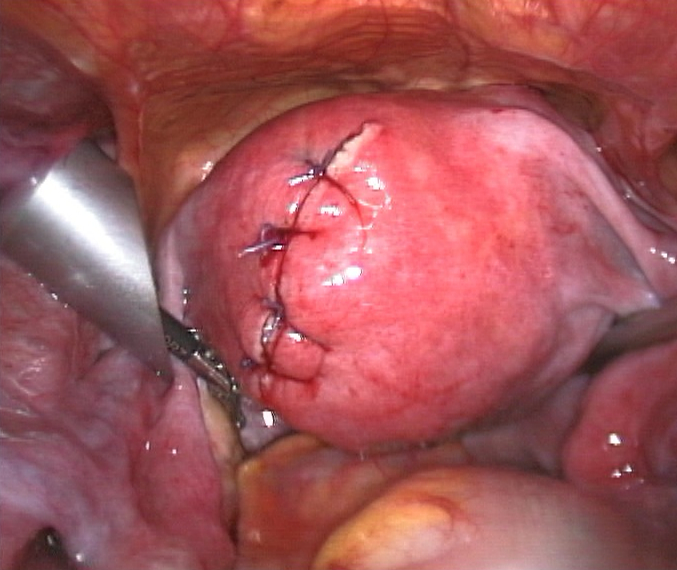

근종 절제술은 하나 이상의 자궁근종을 제거하는 수술이다. 보존적 치료 옵션이 실패하고, 가임력을 보존하거나 자궁을 유지하려는 환자에게 보통 권장된다.[60]

근종 절제술에는 세 가지 유형이 있다.

- ''복강경'' 근종 절제술: 배꼽 근처의 작은 절개를 통해 수행. 의사는 복강경과 수술 도구를 사용하여 자궁근종을 제거. 복강경 근종 절제술이 개복 근종 절제술보다 낮은 이환율과 더 빠른 회복을 보인다.[61]

복강경 근종 절제술은 개복 수술보다 통증이 적고 입원 기간이 짧다.[62] 15,000명의 환자를 분석한 결과, 근종 절제술을 받은 환자는 그 후 5년 동안 자궁근종 관리를 위한 추가 시술(자궁 절제술 포함)이 UAE를 받은 환자보다 적게 필요했다.[63][64]

증상이 있는 경우에는 치료가 필요하다.[79] 치료법으로는, 임신을 희망하는 경우 GnRH유사체 투여로 근종을 축소시킨 후 근종 절제술을 시행하고, 임신을 희망하지 않거나 악성 소견이 보이는 경우에는 단순 자궁 절제술을 시행한다.[82] 근종 절제술에는 복식(개복), 질식, 복강경, 자궁경 하 방식이 있다. 자궁경 하 방식은 장경 3cm 정도의 점막하 근종에 적합하다. 수술 외의 치료법으로는 자궁 동맥 색전술[82]이나 고강도 집속 초음파 치료 등이 알려져 있다.